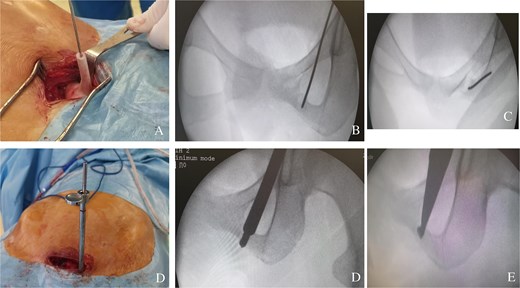

The patient received acetylsalicylic acid, with partial clinical improvement. The decision was made to perform a surgical drilling and curettage of the tumour with the help of a customized 3D-printed guide (Fig. 2A–C). The patient underwent surgery on a standard table, in supine position, under general anaesthesia. A mini-Pfannenstiel approach (on the pubic symphysis) was performed to expose the proximal and medial border of the left iliopubic ramus, which served as a fixed landmark for positioning the guide (Fig. 3A). Once the guide had been pinned in place, a K-wire was inserted in the direction of the tumour. A fluoroscopic check verified the K-wire positioning (Fig. 3B). A soft tissue protection instrument was used to guide the cannulated drill bit towards the tumour (Fig. 3C). Drilling and curettage of the lesion was performed under fluoroscopic control with anteroposterior, inlet, and outlet views of the pelvis (Fig. 3D and E). The anatomopathological examination confirmed the diagnosis of osteoid osteoma, which was completely resected. Pain disappeared in the immediate postoperative period. At 24-month follow-up, we did not note recurrence of the tumour (Fig. 4A and B). Written informed consent was obtained from the patient.

(A) Two customized 3D-printed drill guides for more precision. (B) A customized 3D-printed drill guide with two K-wires positioned in the direction of the tumour. (C) A customized 3D-printed drill guide with one K-wire positioned in the direction of the tumour.

(A) Positioning the guide on the iliopubic ramus via a mini-Pfennestiel approach. (B) Anteroposterior fluoroscopic control of the correct position of the K-wire in the tumour. (C) Fluoroscopic inlet view showing the correct position of the K-wire in the tumour. (D) A soft tissue protection instrument as a guide for the cannulated drill. (E) Curettage of the tumour.